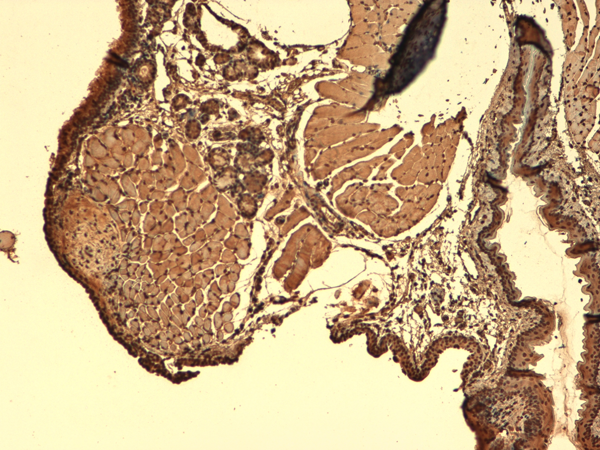

IHC (Immunohistochemistry)

(Immunohistochemistry analysis using Mouse Anti-Sodium Iodide Symporter Monoclonal Antibody, Clone 14F. Tissue: Thyroid. Species: Mouse. Fixation: 10% Formalin Solution for 12-24 hours at RT. Primary Antibody: Mouse Anti-Sodium Iodide Symporter Monoclonal Antibody at 1:1000 for 1 hour at RT. Secondary Antibody: HRP/DAB Detection System: Biotinylated Goat Anti-Mouse, Streptavidin Peroxidase, DAB Chromogen (brown) for 30 minutes at RT. Counterstain: Mayer Hematoxylin (purple/blue) nuclear stain at 250-500 ul for 5 minutes at RT.)